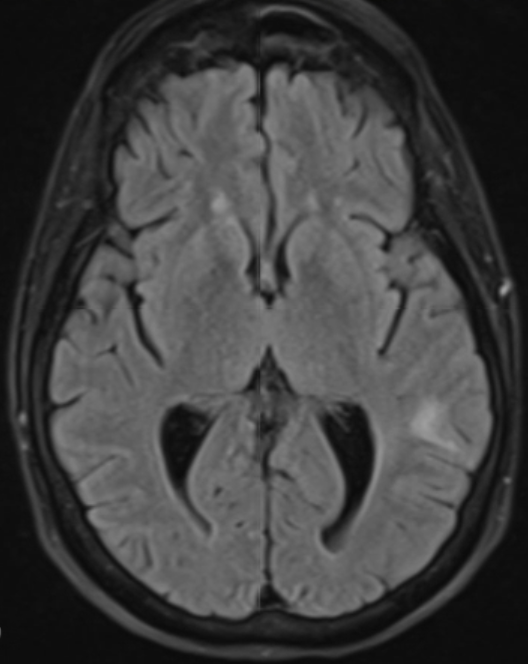

IMAGE 2: Magnetic resonance imaging of the brain showed multiple brain metastases involving the parietal, frontal, temporal lobes, and cerebellum.

Case Presentation: A 61-year-old, non-smoking, white female with history of Coronavirus disease 2019 (COVID-19) twice, and long COVID syndrome, presented with progressively worsening dyspnea over the last five months. She was repeatedly diagnosed with pneumonia and treated with antibiotics and steroids without relief prior to hospital presentation. Workup in the hospital revealed neutrophilic leukocytosis, but no other significant findings. Computed tomography angiography of the chest led to evidence of multifocal bilateral extensive ground glass opacities with consolidation mostly in the right middle and right lower lobes, mediastinal lymphadenopathy, cervical lymphadenopathy, and left axillary lymphadenopathy. The patient was diagnosed with cryptogenic organizing pneumonia. Pulmonology was consulted who decided to perform bronchoscopy for further evaluation, but the patient was unable to tolerate laying supine without dropping oxygen saturation. Thus, conservative management was taken with broad spectrum antibiotics and steroids. Her oxygen requirements increased to 10L/min following discharge. The patient presented again to the hospital three weeks later with acute hypoxic respiratory failure after her oxygen concentrator stopped working from an electricity outage. Given recurrent dyspneic episodes now requiring high flow nasal cannula during the day and bilevel positive airway pressure at night, an in-depth infectious and autoimmune workup was performed. Consultations were made to rheumatology and infectious disease to help with diagnosis. Lab workup was negative. A repeat computed tomography (CT) of the chest was performed which again revealed diffuse bilateral ground glass opacities and mediastinal lymphadenopathy. Physical exam during this hospital encounter was notable for a palpable 1.7 cm, nontender cervical lymph node. She subsequently underwent ultrasound guided lymph node biopsy for further evaluation. Pathology revealed metastatic adenocarcinoma of pulmonary origin. Brain magnetic resonance imaging was performed and revealed at least 8 brain metastases involving the parietal, frontal, temporal lobes, and cerebellum. Additionally, CT of the abdomen revealed a 1.7 cm hypodense lesion in the right hepatic lobe. Overall impression was that of stage IVB T2-3 N3 M1B non-small cell lung cancer, adenocarcinoma subtype.